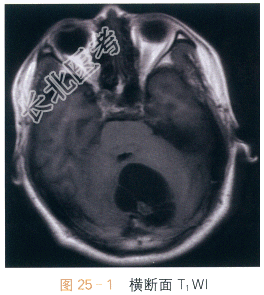

影像学资料如图25-1~图25-4所示。

读片分析:头颅横断面T₁WI示小脑半球囊性占位,呈低信号影,边界清晰,边缘光整,内可见附壁结节,呈等低信号影,第四脑室受压改变;横断面T₂WI囊液呈脑脊液样高信号影;增强扫描可见附壁结节明显强化。结合病史,患者考虑为血管母细胞瘤。